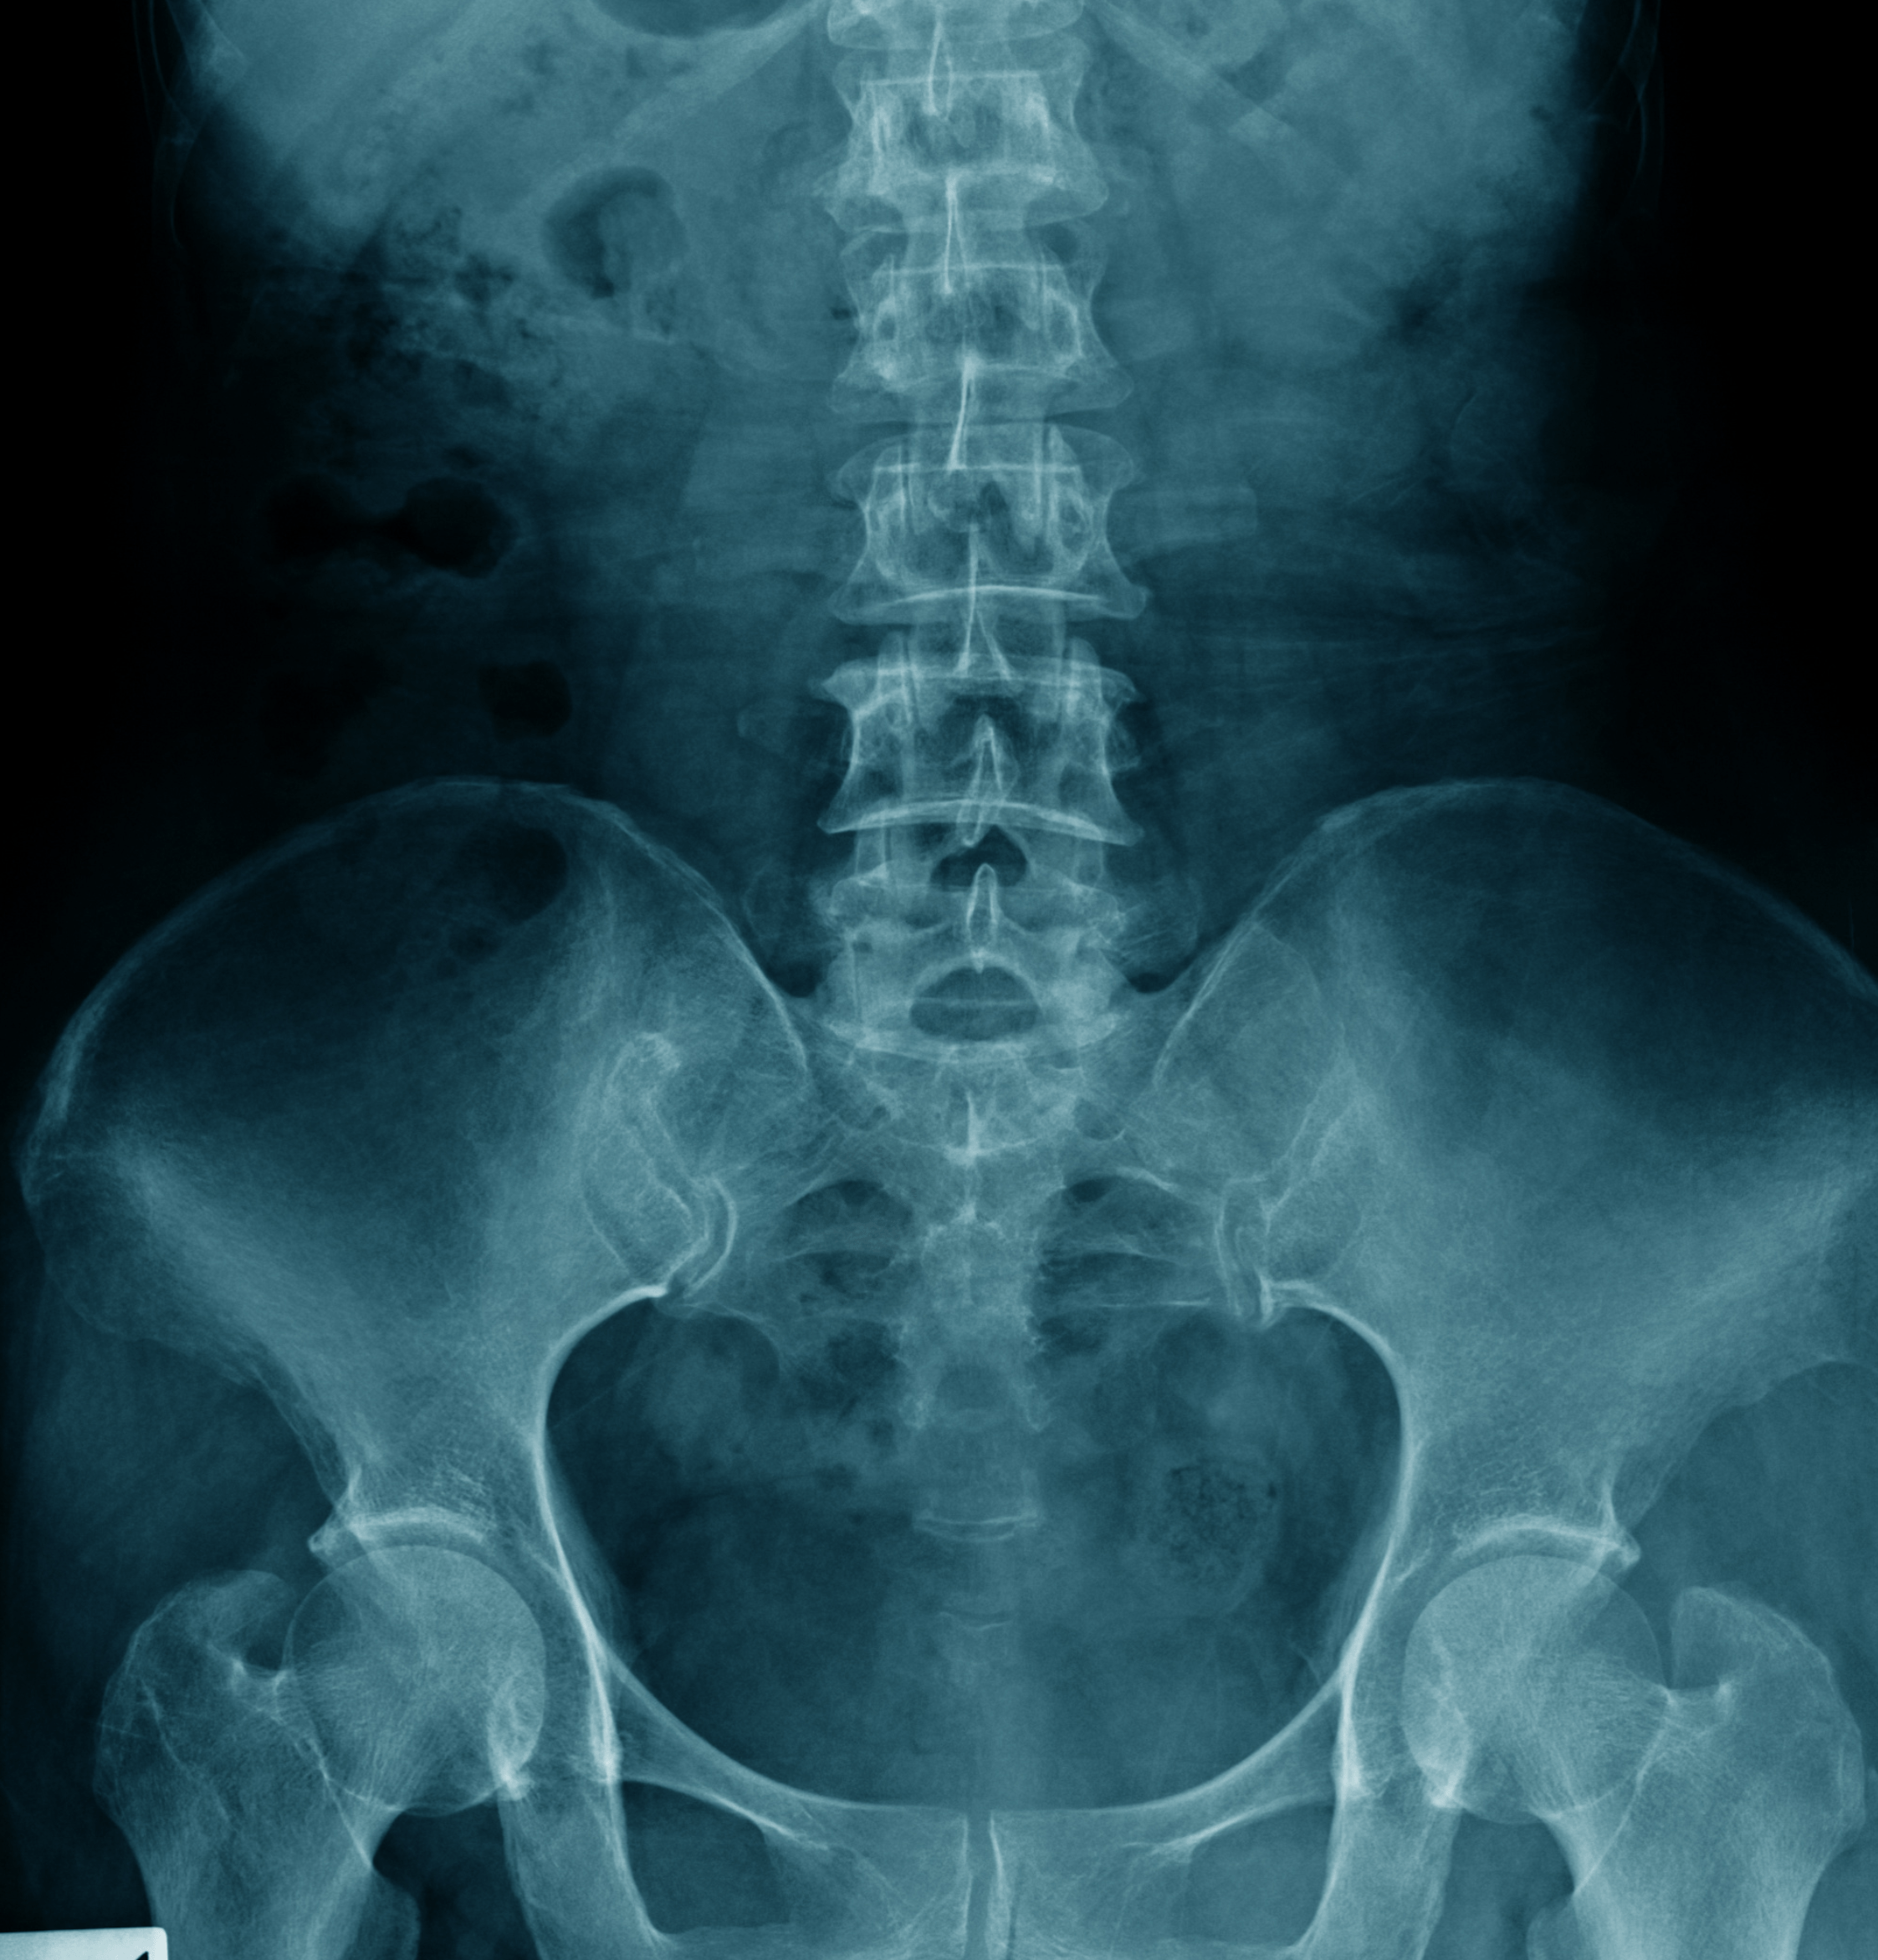

Radiografia Lombare a Domicilio

Radiografia lombare

Che cos'è la Radiografia Lombare?

La radiografia lombare, o RX lombare, è un esame diagnostico che utilizza i raggi X per creare immagini dettagliate delle vertebre lombari e delle strutture circostanti della parte bassa della schiena.

Questo esame permette di visualizzare chiaramente le ossa, che appaiono molto più chiare rispetto agli altri tessuti, e fornisce informazioni utili per valutare lo stato della colonna vertebrale lombare.

A cosa serve la Radiografia Lombare?

La radiografia lombare è utilizzata principalmente per diagnosticare e monitorare condizioni come:

Fratture vertebrali: Lesioni alle vertebre lombari.

Artrite e osteoartrite: Infiammazioni o degenerazioni delle articolazioni spinali.

Spondilosi: Cambiamenti degenerativi delle vertebre e dei dischi intervertebrali.

Ernie del disco: Spostamenti del disco intervertebrale che possono comprimere i nervi.

Scoliosi: Curvatura anomala della colonna vertebrale.

Stenosi spinale: Restringimento del canale spinale.